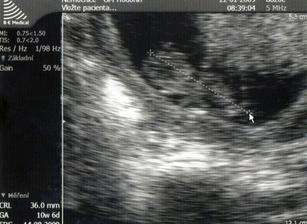

Na kotrolu jsem šla už 15.1. protože mám neschopenku bez vycházek,tak ať mi dr.nějaké napíše.Tak jsem dostala vycházky-konečně.Doma už to bylo na zbláznění.Domluven genet.ultrazvuk na 4.2.*************************************************

4.2. NT screening.Ultrazvuk dopadl na 1.Ještě čekáme na výsledky krve.Ty by měly být v poradně 19.2.Snad bude i tady vše v pořádku.Máme strach.***********************19.2.odběry na NT screening dopadl na 1.Tak aspoň něco.Na ultrazvuku je mimi o něco menší,ale snad to nebude nic znamenat.Příští týden na krev na TT. 19.3. další poradna.A pak se už pojede do Brna na velký ultrazvuk.***********************************30.3. velký ultrazvuk v brně.Držte nám pěsti,ať je vše OK.****************************************30.3. ultrazvuk v brně dopadl na 1.Mimi je v pořádku a hlavně,čekáme HOLČIČKU.******************************************************************************